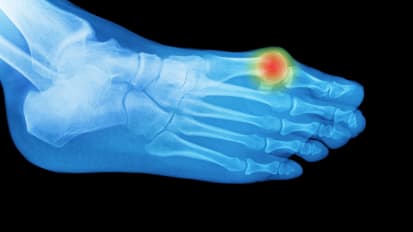

There’s No Reason to Put Off Bunion & Hammertoe Corrections

Patients, young and old, can benefit greatly from routine surgery for bunions and hammertoes. The specialists at Emory Orthopaedics & Spine Center have been researching the best ways to treat toe and forefoot deformities for years and ...